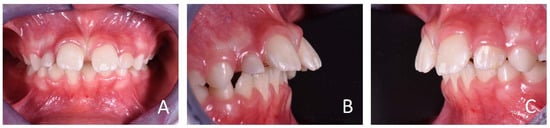

3.1. Clinical Case #1

3.2. Clinical Case #2

3.3. Clinical Case #3

3.4. Clinical Case #4